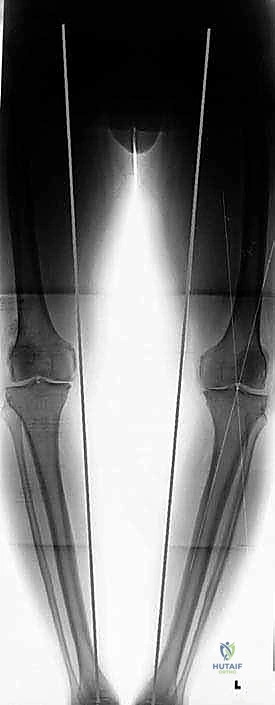

في الحالة الطبيعية الميكانيكية، يمر "محور تحمل الوزن" (Weight-bearing axis) مباشرة عبر منتصف الركبة، مما يوزع الضغط بالتساوي. ولكن، عند حدوث تقوس في الساقين (Varus Deformity)، ينزاح هذا المحور إلى الداخل، مما يضع ضغطاً هائلاً ومدمراً على الغضروف الداخلي للركبة.

تُعد الأشعة السينية (X-rays) الممتدة من الحوض إلى الكاحل (Scanogram) ضرورية جداً لحساب زاوية التقوس بدقة وتحديد مقدار التعديل المطلوب جراحياً.

قبل العملية، يتم قياس زوايا الركبة بدقة متناهية. كل درجة من درجات التعديل يتم حسابها مسبقاً.

استخدام التخطيط الرقمي يضمن عدم حدوث تصحيح مفرط (Over-correction) أو تصحيح ناقص (Under-correction)، وهو ما يميز الجراح الخبير عن غيره.